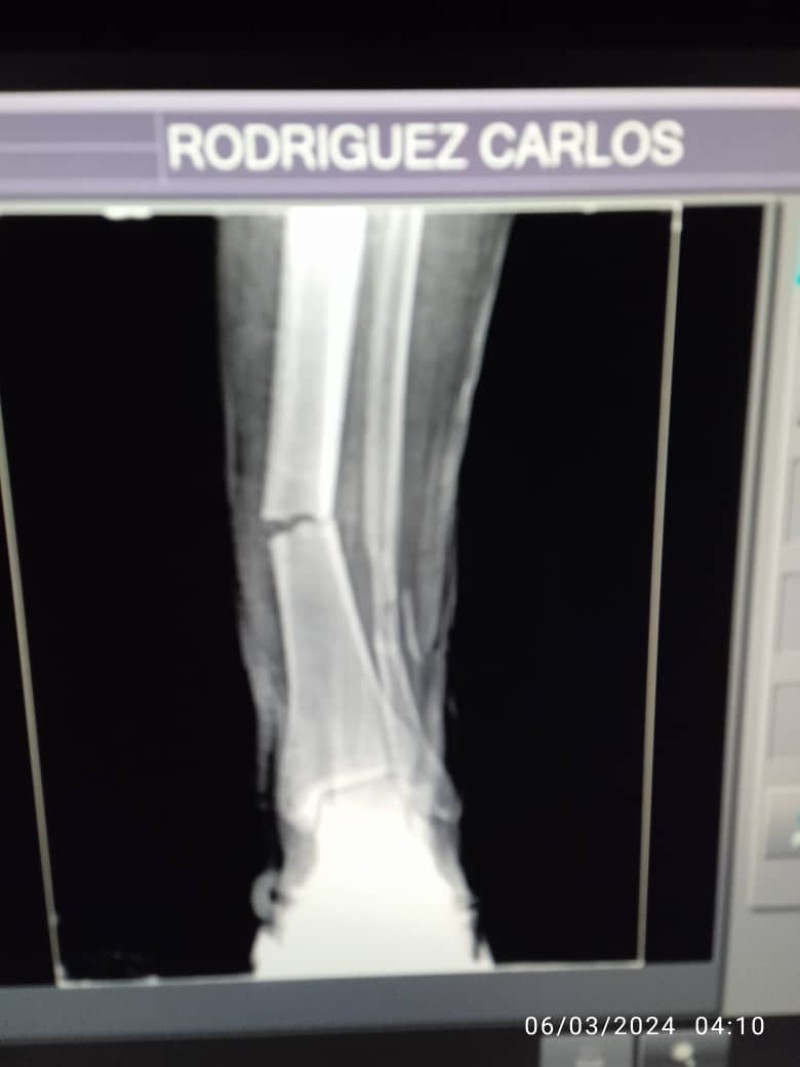

Hello, My name is Carlos Rodriguez, I'am a 36 years old natural venezuelan, and recently i had a motorcycle accident, i got to bones broken in my the lower part of my left leg and i need to go under surgery, i do not have the money to pay the meds and the surgeons, but if you can help me, i'd be very gratefull.